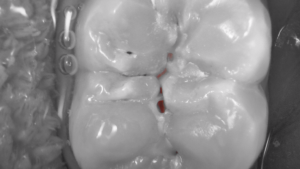

• Mode cario  : Détection des caries grâce à la technique de Fluorescence par LEDs